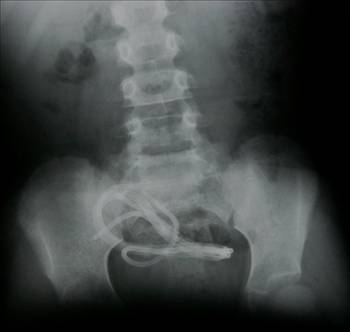

Bir marangozhanede çalışan işçiler iş çıkışı üzerlerindeki talaşları kompresör ile temizlemektedirler. Bu arada arkadaşına yardımcı olan isçi Ali, şaka olsun diye, Burhan’ın neticesine dogru hava tutar. Buna içerleyen Burhan, ‘Öyle şaka olmaz böyle olur’ diyerek hava tabancasini alır ve arkadaşı Ali’nin makatına sokar.Bağırsakları patlayan Ali hastane yolunda Hakk-ın rahmetine kavuşur. (İstanbul, Ayazağa Sanayi Sitesi)